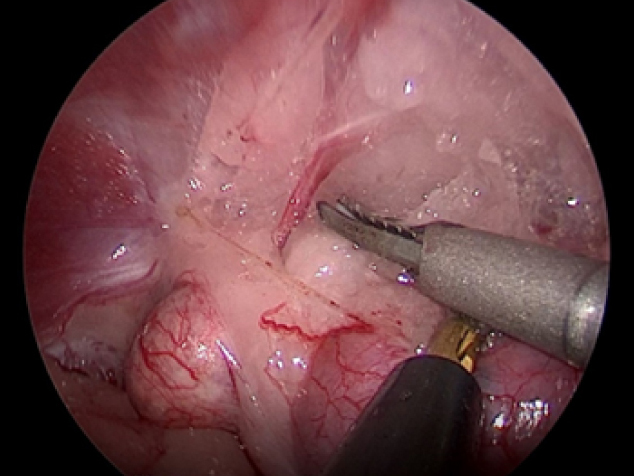

まずは腎臓、副腎と腹壁がくっついているところをはがしていきます。 脂肪の中に血管が隠れているのでそれを出血させないように丁寧にはがしていきます。 血管は電気メスや超音波メスを使って止血していきます。

実際の手術風景です。

犬の右副腎2.5cm。腹腔鏡下手術。3ポートで摘出が可能。

CLARA&CROMAという新しいモードで手術している。

これは暗いところ明るくし、CROMAは赤を強くしコントラストをつけることにより血管一本までしっかりと確認することができる。

少しギラギラするが、手術しやすくなる。